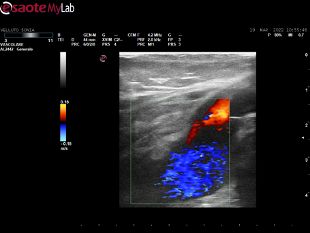

Svolgo attività quotidiana di diagnostica vascolare non invasiva, di cura delle arteriopatie e di tutte le patologie venose: varici, trombosi venose profonde acute, sindrome post-trombotica, ulcere venose e/o linfatiche, edemi degli arti inferiori, ulcere croniche.

• Ecocolordoppler vascolare

120 €